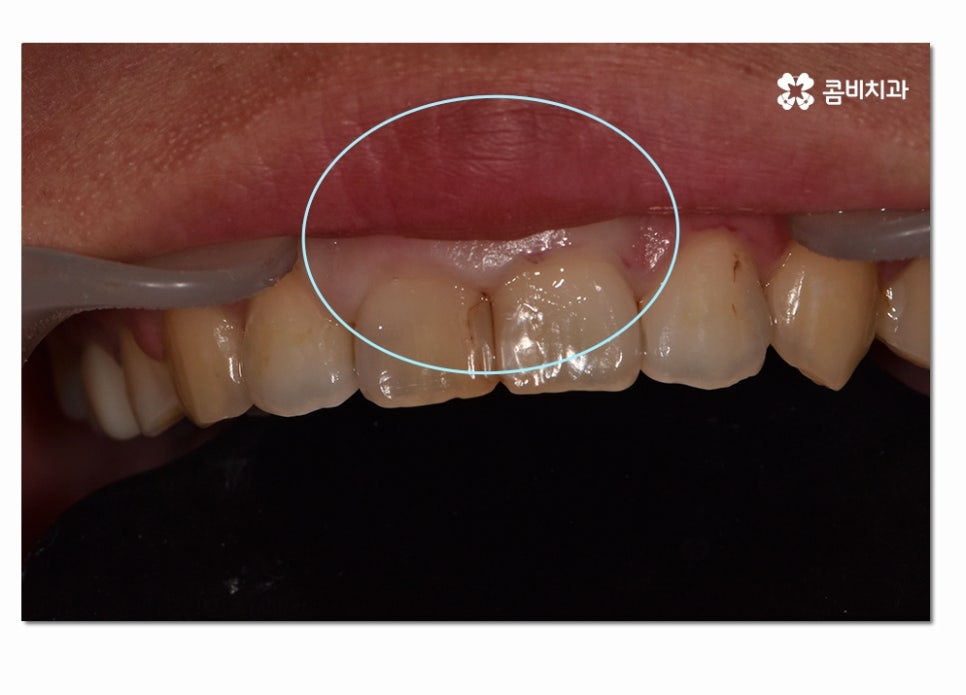

수술적인 치료 방법은 치은절제술과 치은성형술,치주판막술,치주성형술 등을

예로 들 수 있으며 오늘 소개 드리고자 하는 케이스는

치은절제술에 해당하는 치료 방법으로 너무 늦지 않게 치료하여

잇몸과 치아를 건강하게 살린 케이스라고 말씀드릴 수 있어요.

이러한 수술적인 방법은 잇몸을 절개하고 치은 깊숙하게 숨어 있는

치석을 제거해 주거나 치주조직이 다시 건강하게

회복될 수 있도록 형태를 바꿔주며 재생을 돕는 방법이라 할 수 있는데요.